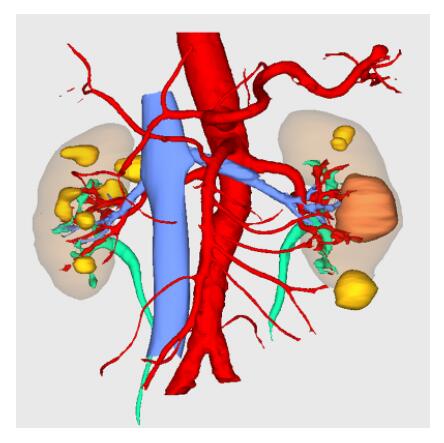

Segmentation

Segmentation of tissue (e.g., isolating the brain, differentiating gray and white matter) is performed using region-growing methods, filter operations as well as the application of 3D templates. Using the mouse it is very easy to explore a 3D volume with superimposed pseudocolor-coded statistical maps in a four-window representation showing a sagittal, coronal, transversal and oblique section. Based on a (segmented) 3D data set a three-dimensional reconstruction of the subjects' head and brain can be calculated and displayed from any specified viewpoint using volume or surface rendering.

Volume Rendering

Volume rendering is performed with a very fast ray casting algorithm; lightning calculations are based on Phong-shading. Surface rendering of reconstructed surfaces is performed using OpenGL. Using texture mapping, a reconstructed surface (e.g., head or brain) may be sliced in real time, showing both surface and volume data at the same time. Initial polygon meshes serve as the basis for surface finding, cortex inflation and cortex flattening computations.